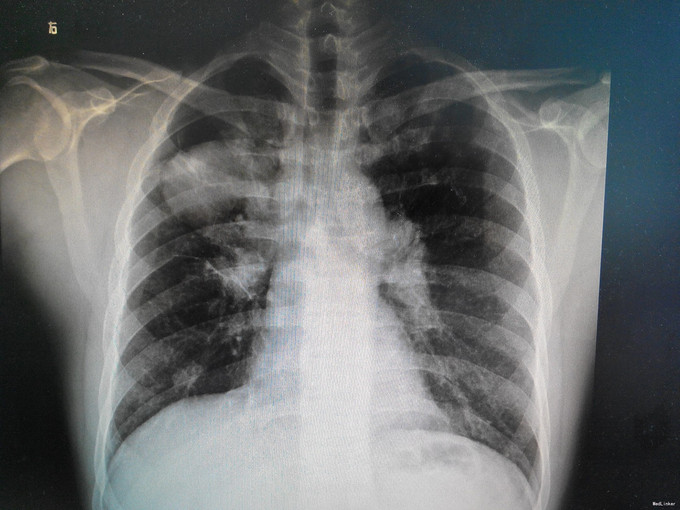

患者男,20岁,发热10天,伴咳嗽咳痰7天,加重2天。 患者于2015-10-12受凉后出现咽痛、畏寒发热,最高体温38.5℃,伴头痛、肩关节酸痛,无咳嗽咳痰,无胸痛胸闷等,遂至当地医院就诊,予左氧氟沙星、阿莫西林克拉维酸钾抗感染,布洛芬退热治疗2天,体温降至正常,自行停药,后出现咳嗽、咳少量白痰,10-21再次发热,体温未测,咳嗽咳痰明显加重,呈剧咳,咳黄脓痰,痰中偶有锈色血丝,伴胸痛、气促,活动后加重。遂来我院门诊,查胸片示:右肺炎症,以 ”肺炎“收住院。既往身体一般。

查体:精神稍萎,双上肺呼吸音稍粗,右肺可闻及少量湿罗音。心脏腹部查体未见异常。 辅查:血常规:白细胞计数10.1×10^9/L、中性粒细胞百分数79.80%;感染指标:CRP48.6mg/L、PCT0.139μg/L;血生化等未见明显异常;多次痰培养阴性。胸片如图示。

诊治经过:考虑为社区获得性肺炎,予头孢替安+莫西沙星经验性抗感染治疗7天,并予雾化吸入,化痰等治疗,患者连续3天无再发热,咳嗽咳痰较前明显好转,复查胸片示肺部炎症较前吸收,血象、感染指标较前好转,考虑抗感染治疗有效,遂改予口服抗生素并办理出院。

讨论:本例由于患者前期不够重视,治疗不规范,入院时已发展为比较典型的大叶性肺炎,甚至出现过铁锈色痰,根据社区获得性肺炎(CAP)病原体分布,选用二代头孢+莫西沙星经验性抗感染,其治疗效果也比较明显。